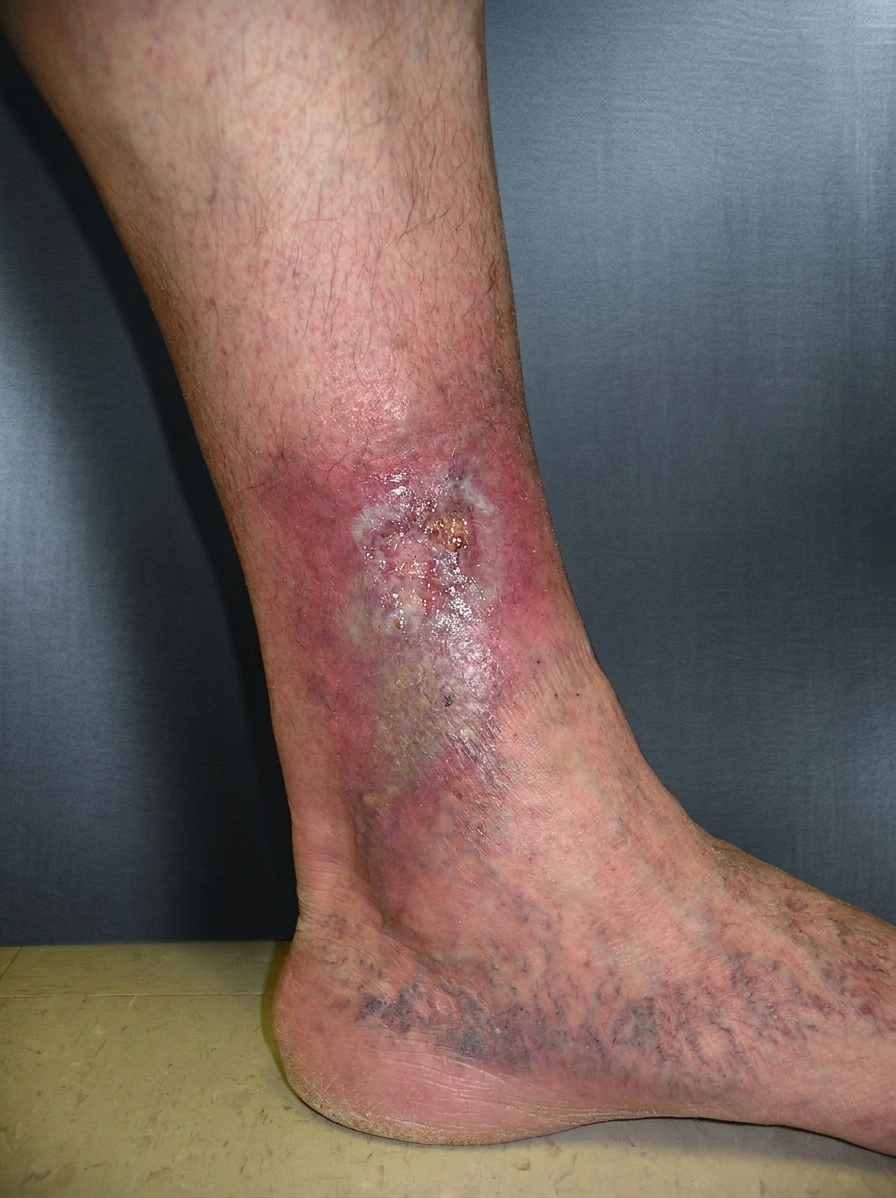

A varicose ulcer (venous ulcer) is a form of venous ulcer caused by long-standing varicose veins and chronic venous disease. Enlarged and twisted veins allow blood to flow backward and pool in the lower leg, increasing pressure and damaging the skin over time.

These ulcers usually appear around the inside of the ankle and are often associated with visible bulging veins, leg heaviness, aching, swelling, and skin changes such as redness, dryness, or dark staining before the ulcer forms.

Venous leg ulcer

Diagnosis involves a clinical examination and a venous ultrasound scan to map the veins and assess valve function. Leakage of the valves leads to a condition called venous insufficiency, which is the underlying cause of varicose veins.

Treatment includes wound care, compression therapy, and treatment of the underlying varicose veins. Varicose vein treatment with endovenous ablation (Venaseal, RFA) or sclerotherapy can close the leaking veins and reduce the chance of the ulcer returning.